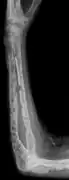

X-ray of the forearm, with lytic lesions

The diagnostic examination of a person with suspected multiple myeloma typically includes a skeletal survey. This is a series of X-rays of the skull, axial skeleton, and proximal long bones. Myeloma activity sometimes appears as "lytic lesions" (with local disappearance of normal bone due to resorption). And on the skull X-ray as "punched-out lesions" (pepper-pot skull). Lesions may also be sclerotic, which is seen as radiodense.[47] Overall, the radiodensity of myeloma is between −30 and 120 Hounsfield units (HU).[48] Magnetic resonance imaging is more sensitive than simple X-rays in the detection of lytic lesions, and may supersede a skeletal survey, especially when vertebral disease is suspected. Occasionally, a CT scan is performed to measure the size of soft-tissue plasmacytomas. Bone scans are typically not of any additional value in the workup of people with myeloma (no new bone formation; lytic lesions not well visualized on bone scan).